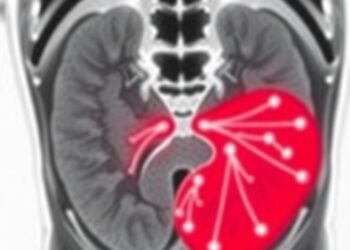

Innovative Imaging Technique Shows Promise in Boosting Survival Rates for Patients with Recurrent Prostate Cancer

A groundbreaking multicenter study spearheaded by the London Health Sciences Centre Research Institute (LHSCRI), in collaboration with the Lawson Research ...